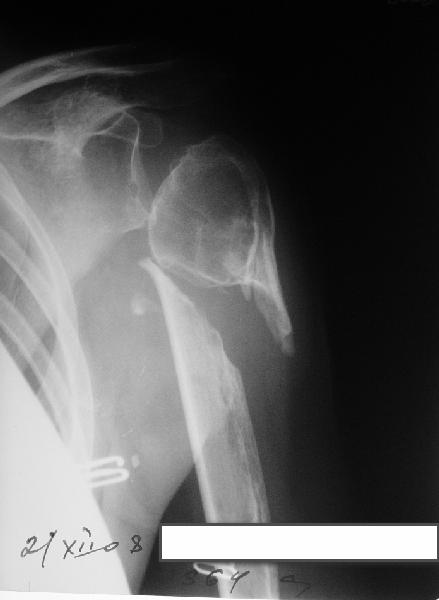

Несращение плеча, деформация головки

Здравствуйте уважаемые коллеги.Помогите, пожалуйста, определиться с тактикой.Больная 40 лет, множественная травма в июне 2007 года. Лечилась в городской больнице.

Повреждение проксимального отдела плеча вели консервативно в гипсовой повязке. В настоящее время больную беспокоят боли в области плечевого сустава, слабость верхней конечности. Амплитуда движений в плечевом суставе в пределах 30-40 градусов. Пациентка хотела бы увеличить объем движений и силу.Движения сейчас в основном за счет ложногго сустава. Варанты - остеосинтез, артролиз, эндопротезирование, оставить как есть. Как-то н один однозначно не привлекает.